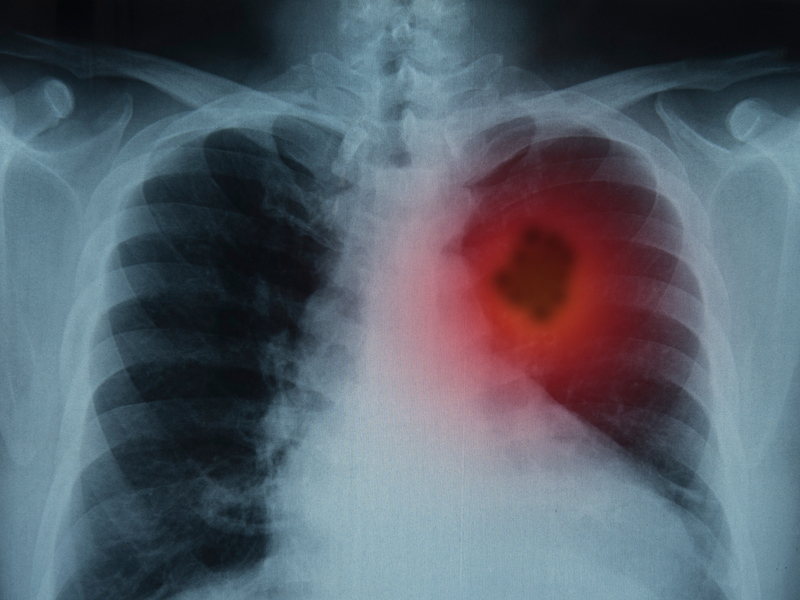

1、頻繁乾咳

咳嗽是非常常見的症狀,並不是所有咳嗽都與肺癌有關。但若本身屬於高危人群,且咳嗽遲遲不見好轉,並伴有痰中帶血、聲音嘶啞,乾咳持續,且夜晚有加重症狀,甚至會影響睡眠,就要警惕是肺部腫瘤引起。

2、胸背部疼痛

肺癌會侵犯相鄰的胸膜或胸壁,這兩個部位神經密佈,神經組織受損,可引起炎症反應。當癌細胞進一步侵犯,就會引起尖銳和斷續的胸膜性疼痛。

3、喘鳴

癌細胞侵犯,可影響支氣管道,引起支氣管粘液大量分泌,肺部炎症物質增多,這兩種物質都會導致患者呼吸不暢,出現呼吸困難的情況。在睡覺時,就會感覺胸悶氣短,導致喘氣聲過大,出現喘鳴症狀。

4、發熱

癌細胞需要不斷吸收人體營養進行繁殖,當人體供不應求,癌細胞就會出現供血不足壞死,從而引起人體炎症發熱。尤其是夜間,人體處於非活動狀態,發熱就容易被機體察覺,不少患者應身體發熱而醒。